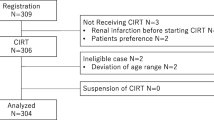

In total, 253 consecutive patients with prostate cancer treated with CIRT at KCC between December 2015 and December 2017 were analyzed in the present study. Clinical records were collected in April 2020. The eligibility criteria for this study were as follows: (i) histological diagnosis of prostate adenocarcinoma, (ii) cT1bN0M0 to T3bN0M0 according to the 7th UICC classification, (iii) performance status of 0–2, (iv) age of 20 years or older, and (v) no previous treatment for prostate cancer excluding androgen deprivation therapy (ADT). The patients were classified using the D’Amico risk group classification [21]. The study was approved by the institutional review board of KCC (approval number: 2019–145). Written informed consent was obtained from all patients.

Patient characteristics are summarized in Table 1. The median age was 70 (range, 47–86) years. The median follow-up duration was 35.3 (range, 4.1–52.9) months. Among 253 patients, 8, 88, and 157 patients were classified as having low, intermediate, and high risks, respectively. The median ages in the low-, intermediate-, and high-risk group were 68 (range, 59–75), 68 (range, 48–81), and 70 (range, 47–86) years, respectively. Significant difference was observed between the intermediate- and high-risk groups (p = 0.034). All patients completed CIRT on schedule. ADT was administered to 244 patients, and the median duration of ADT was 22.8 (range, 2.3–116.9) months. A total of 4 patients underwent transurethral resection of the prostate (TURP) in a median of 14 (range, 9–15) years before CIRT. Of these 4 patients, 2 were classified as intermediate-risk group and 2 as high-risk group.